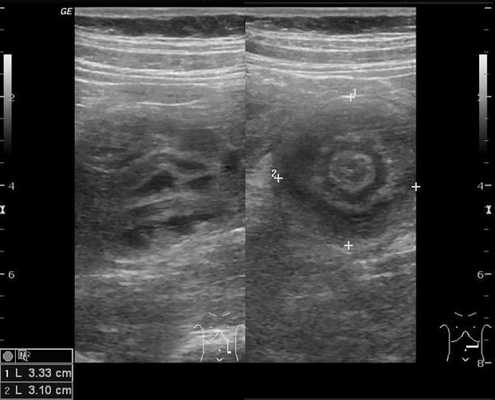

Золотым стандартом считается проведение ультразвукового исследования (сонографии) органов брюшной полости, так как оно является неинвазивным, быстрым, безопасным, безболезненным и высоко информативным методом. [9] [10] При помощи сонографии можно диагностировать инвагинат не только на типичных, но и на атипичных участках кишечника, что повышает точность установления и верификации диагноза.

В момент УЗ-исследования врач может определить один из симптомов:

- симптом мишени (за счёт внедрения одной кишки в другую инвагинат на срезе выглядит как мишень);

- симптом "почки с завоздушенным центром".

Для визуализации инвагината проводится УЗИ брюшной полости: определяется гипоэхогенное образование с участком гиперэхогенности в центральной части. Также может применяться ультразвуковая допплерография с целью оценки кровотока в сосудах брыжейки. Обзорная рентгенография брюшной полости обладает меньшей чувствительностью при обнаружении инвагината, но применяется как скрининговый метод исследования при острой боли в животе с целью исключения перфорации, обструкции.